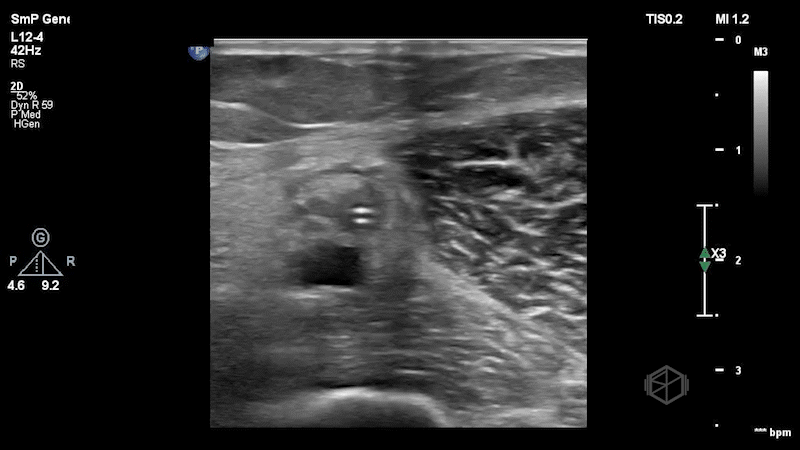

The clips here show the midline catheter in the brachial vein (paired brachial artery underneath). The catheter is surrounded by thick echogenic material - a clot, and is non-compressible. In this case, POCUS usage accurately was able to see the issue with the line.

Diagnosis: Catheter-associated deep venous thrombosis of the brachial vein